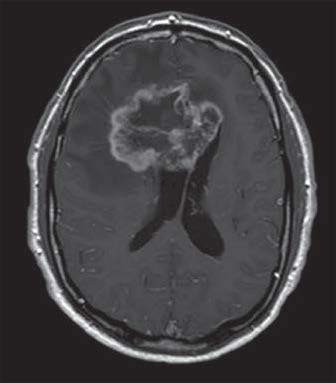

IRM d’un homme de 64 ans atteint d’un glioblastome